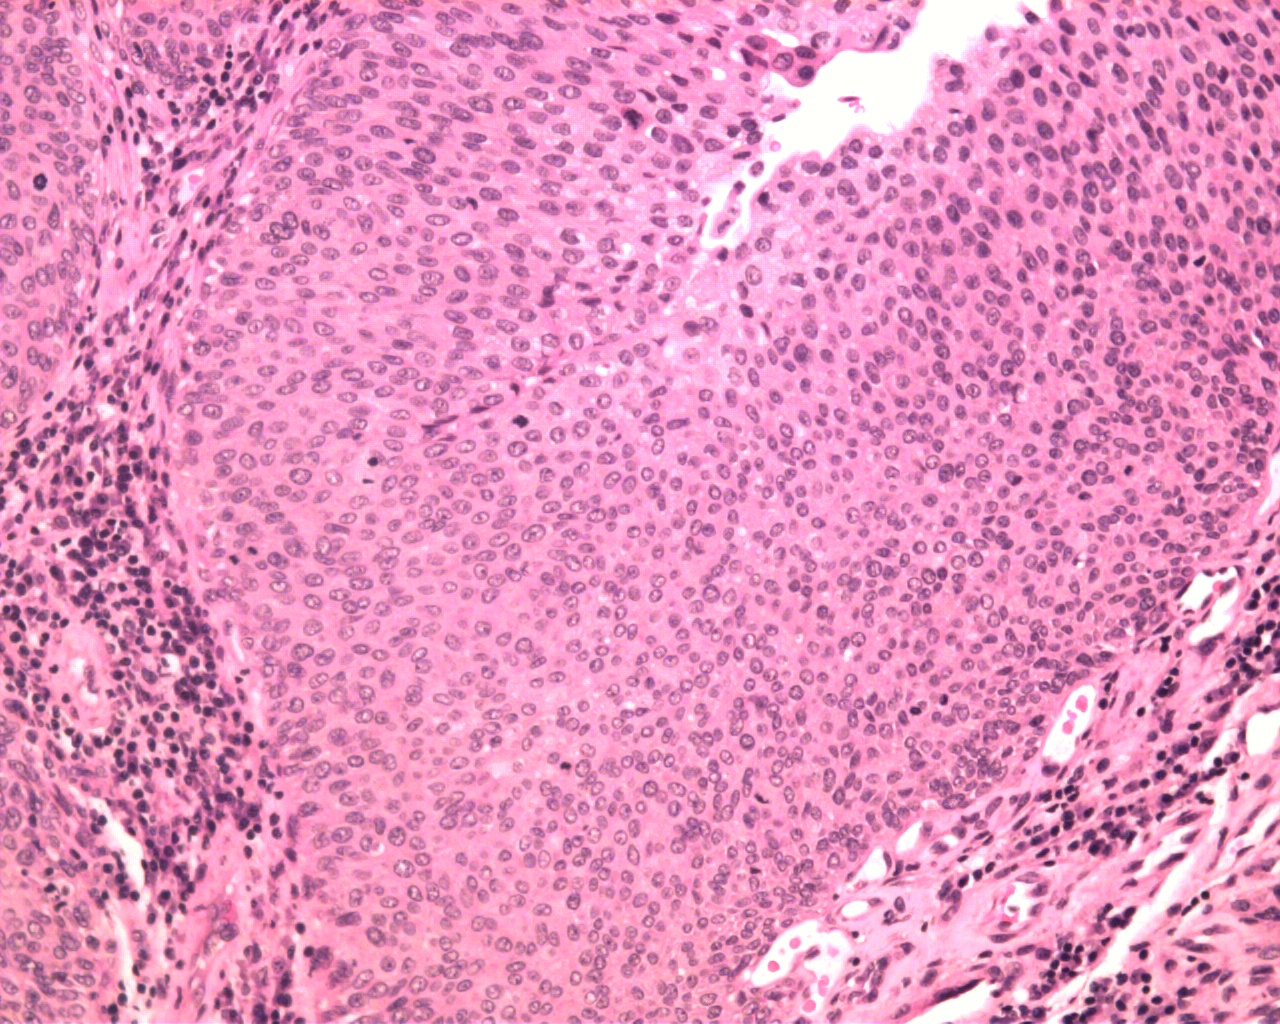

Case ID: 625

Consensus grade: Low-grade papillary urothelial carcinoma (LG-PUC)

Case description (by case creator):